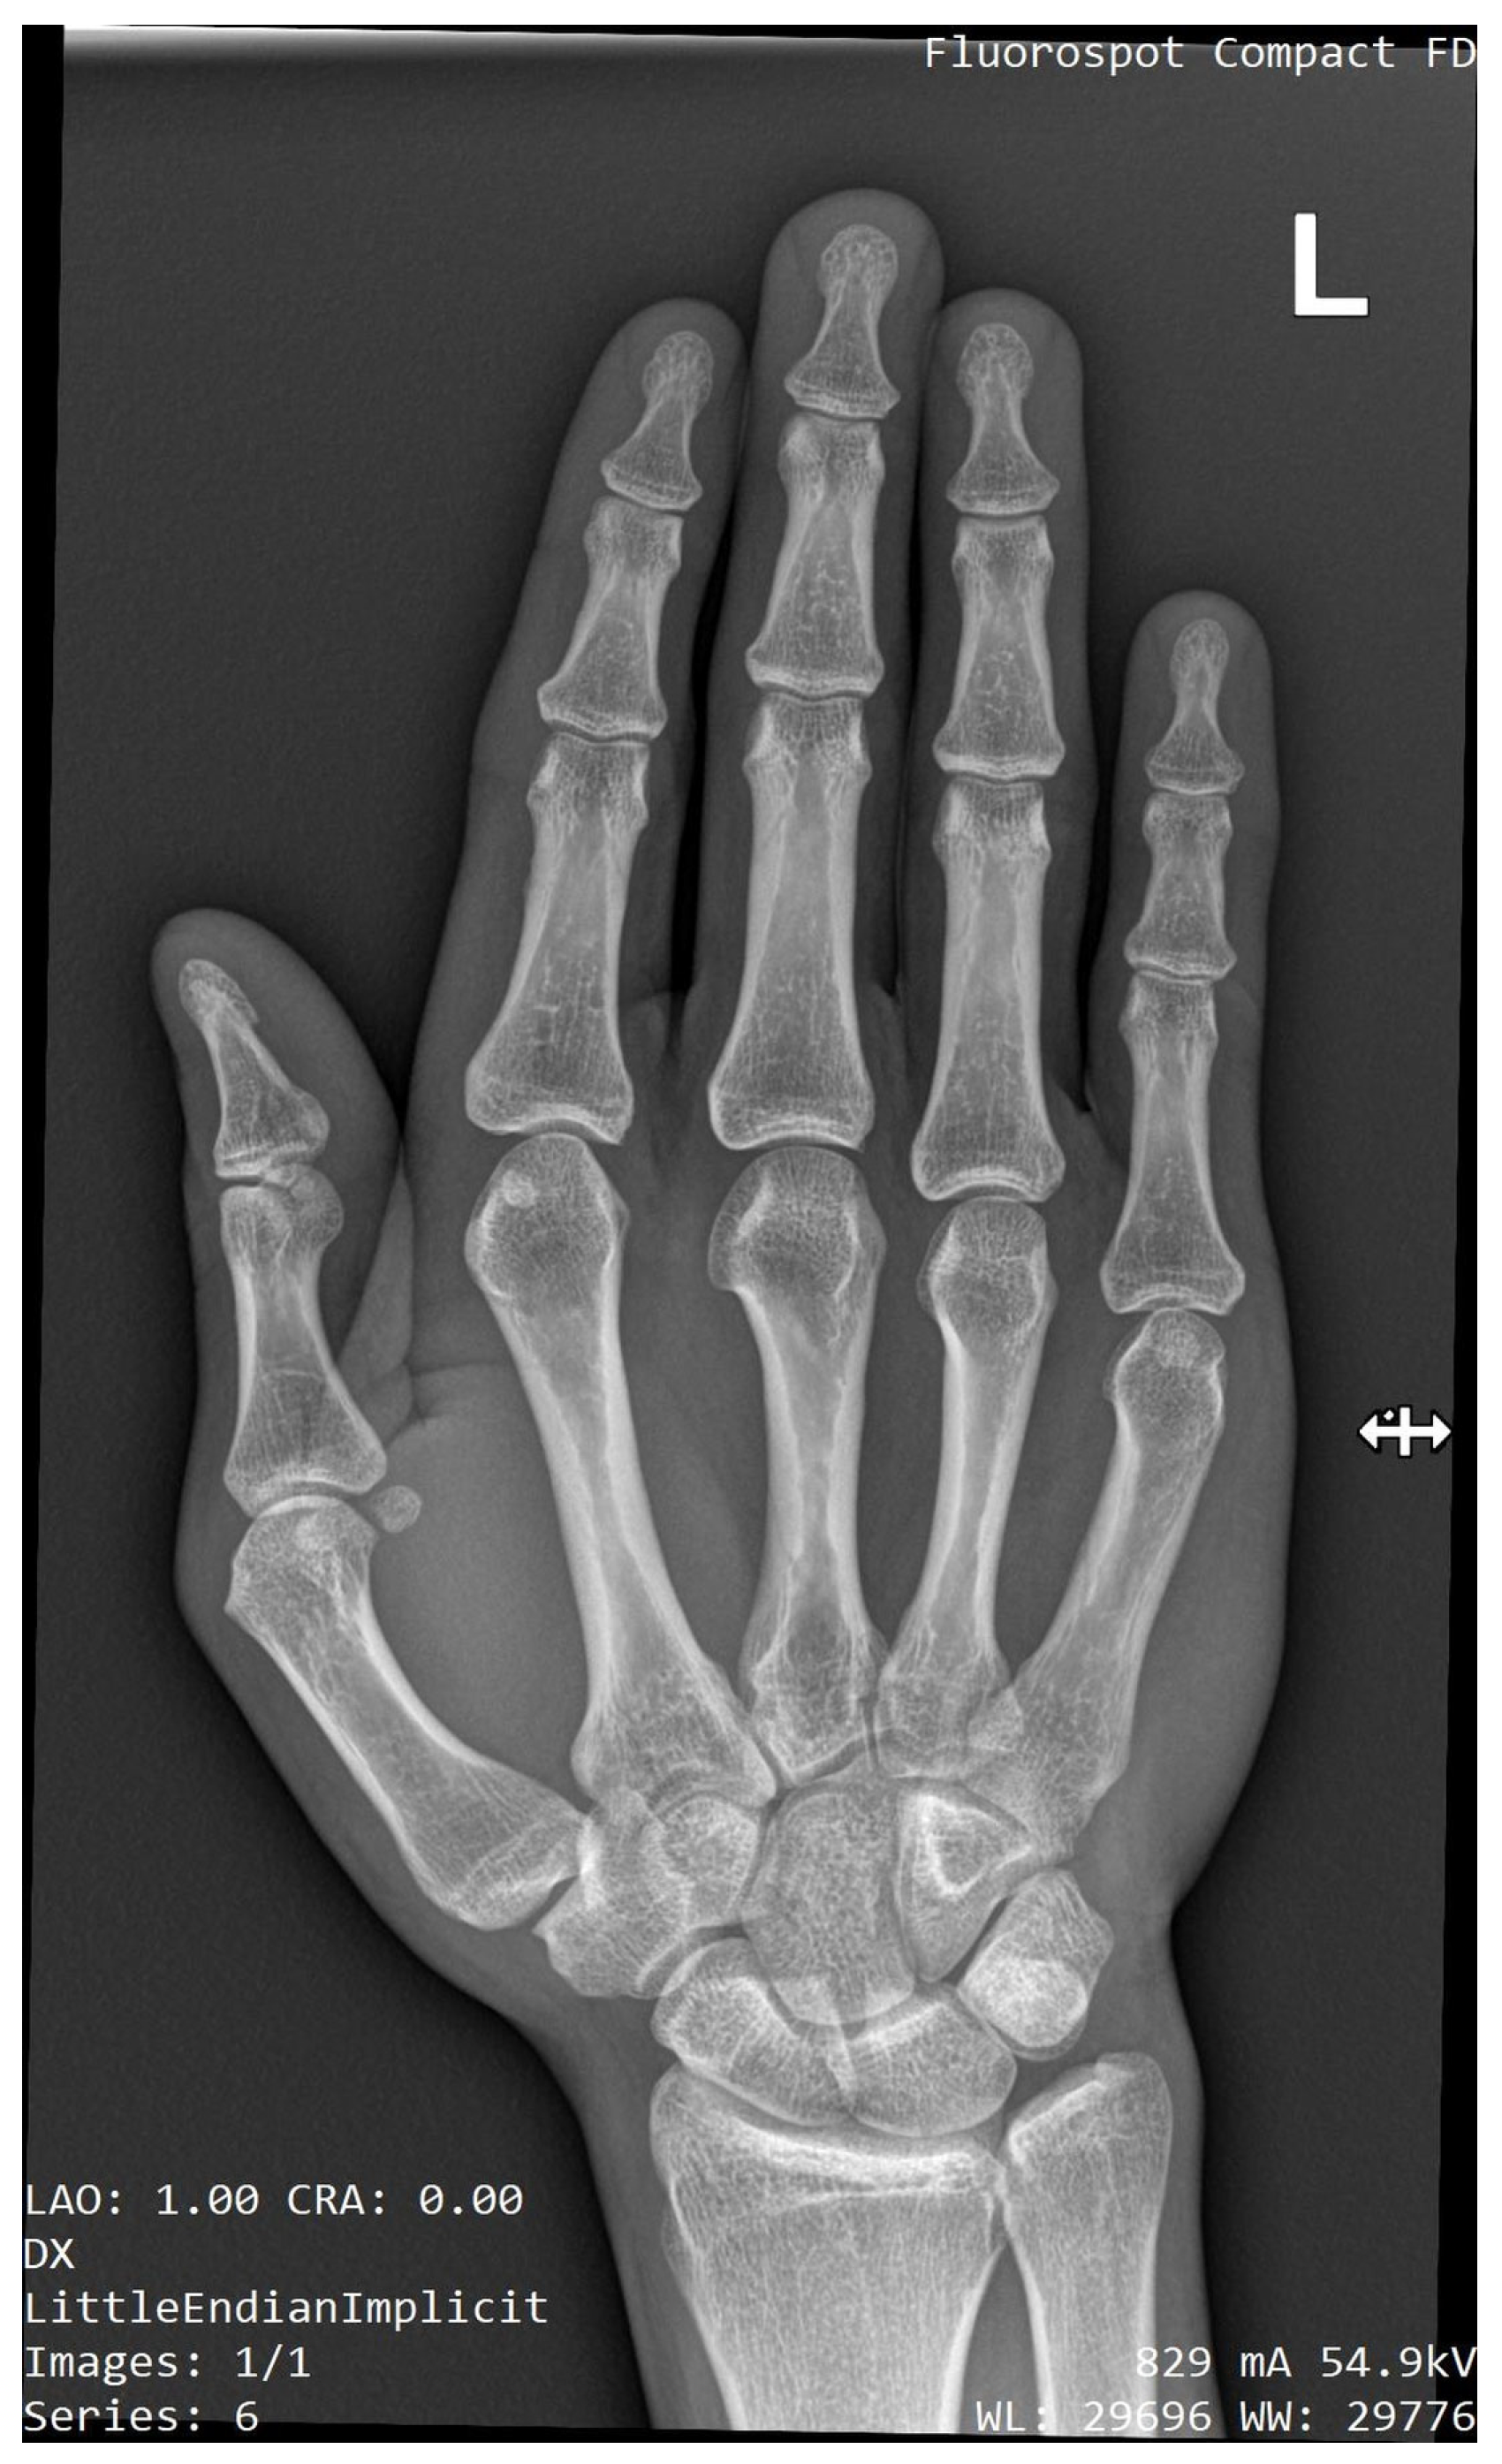

2.2. Radiographic Evaluation